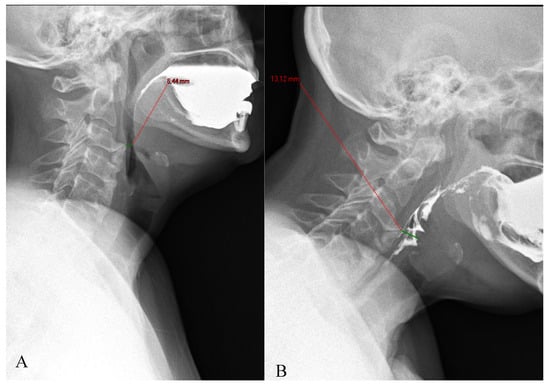

Figure 5. The compensatory position with anterior neck flexion (B), allows the patient to increase the pharyngeal diameter at the level of the narrowing related to the C2 osteophytes, compared to the neutral neck position (A).